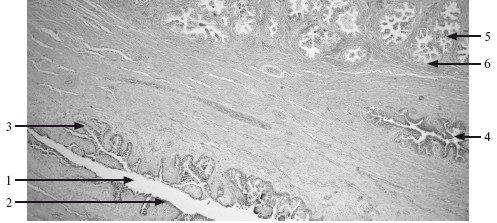

Рис. 18.1. Яичко (семенник) человека. х 132.

1 – извитой семенной каналец; 2 – базальная мембрана; 3 – сперматогонии; 4 – сперматоцит I порядка; 5 – ранняя сперматида; 6 – сустентоцит; 7 – интерстициальная клетка.